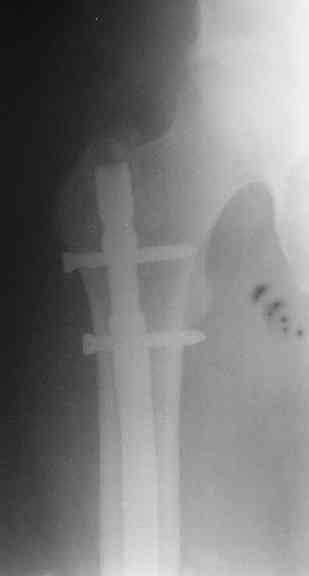

Судя по уровню перелома, винты в шейку избыточны, подойдет и диафизарный гвоздь. Все, что нужно, это тиски и труба. Загнуть сразу ниже отверстий градусов на 8-10, и вся недолга. Последние годы у нас это рутинная практика. Предызогнутые еще с завода гвозди неудобны тем, что они уже правый-левый.

Согласен, что закрытый реостеосинтез с рассверливанием и коррекцией оси - это то, что надо. Мы бы ввели в центральный отломок статических 2-3 винта, и один динамический винт в дистальном отломке.

Вот несколько. С тисками и трубой на днях сделаем.